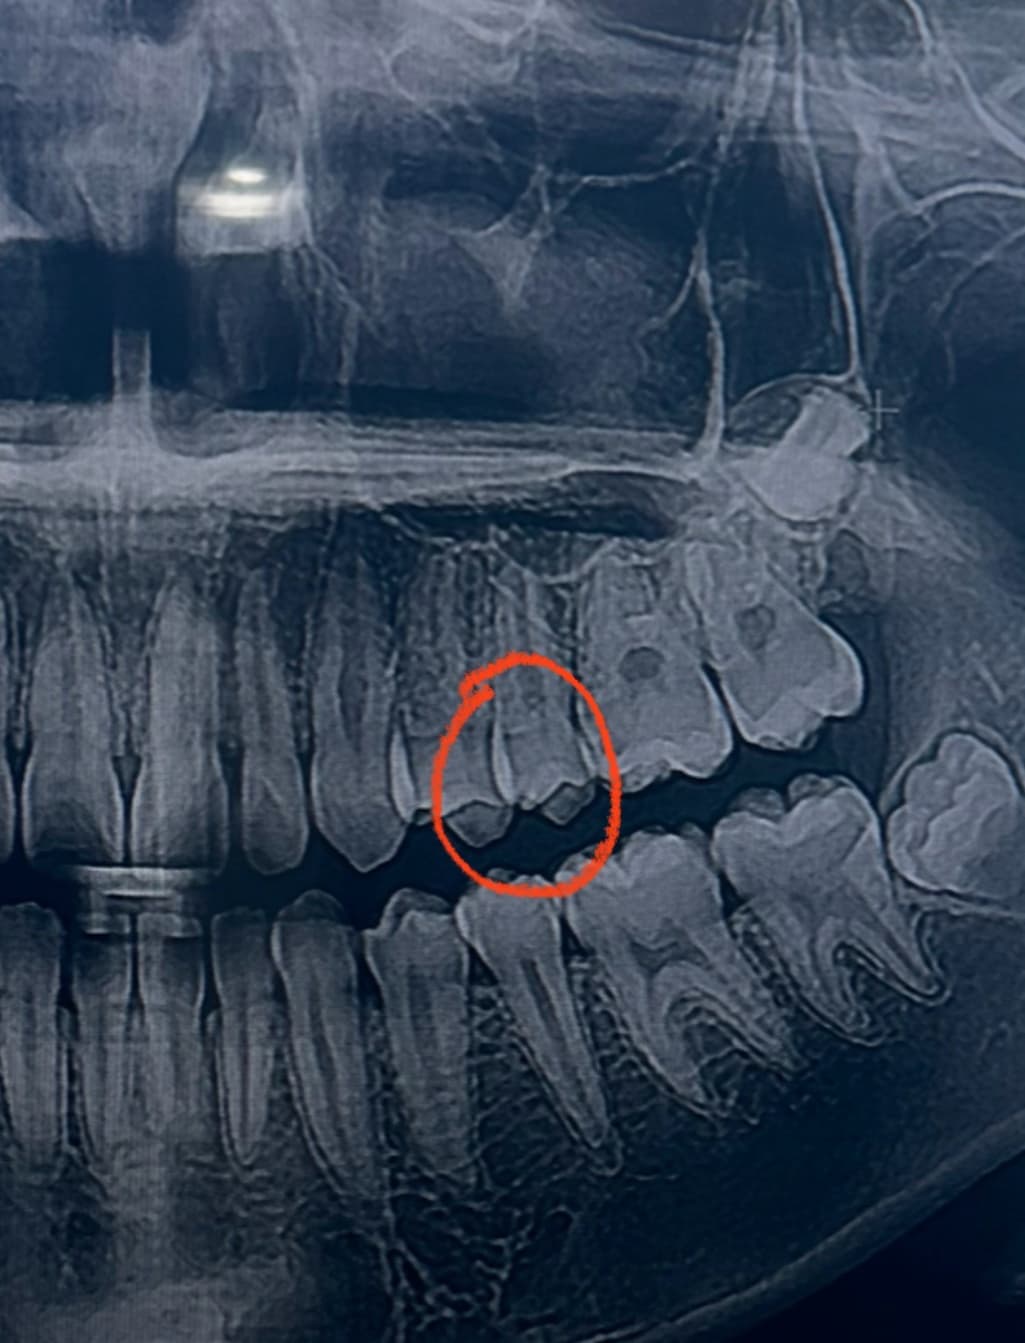

25~26 치아고 첫번째, 세번째 사진이 최근 두번째 사진이 올해 2월 입니다 인접면 충치가 맞는지 얼마나 진행되었는지 궁금합니다

25~26 치아고 첫번째, 세번째 사진이 최근 두번째 사진이 올해 2월 입니다 인접면 충치가 맞는지 얼마나 진행되었는지 궁금합니다 -> 25,26 사이 인접면 충치 크게 문제 없어 보입니다